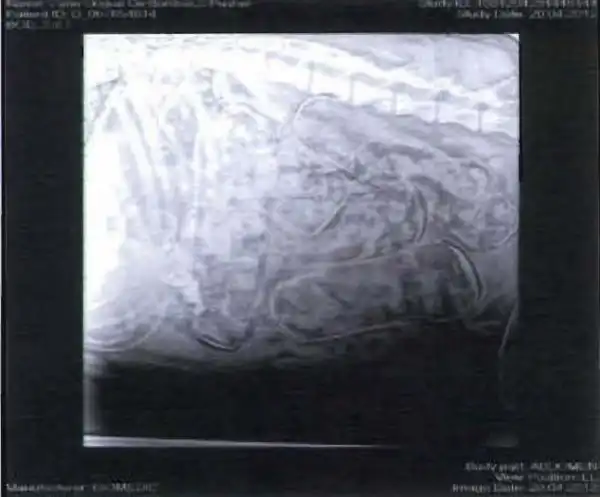

Итальянская полиция задержала банду наркоторговцев которые распространяли наркотики по всему миру,всего было задержано 75 человек на севере Италии и в Риме.Полицию и общественность шокировал метод переправки наркотиков в заграницу,я сам шоке!Эта шайка придумала способ переправке через границу наверное самый жестоки из которых я знаю.